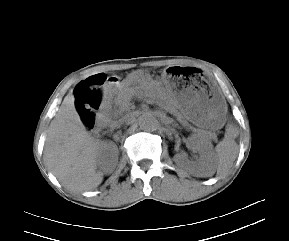

病变位于肝胃间隙,实际就是位于小网膜囊(左肝下后间隙),呈轻度不均匀性强化,腹腔内及腹膜后见多发肿大淋巴结。所以我考虑肝胃间隙恶性胃肠间质瘤并淋巴结转移。

病灶强化不显著,灶周及腹膜后见多量淋巴结肿大,考虑淋巴瘤可能,其次考虑间质瘤

病灶强化不显著,灶周及腹膜后见多量淋巴结肿大,考虑淋巴瘤可能,其次考虑间质瘤。

肝胃韧带内及腹膜后可见多发增大的淋巴结影,首先考虑转移.